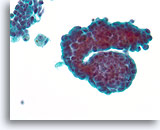

Benigne ductale cellen, Borst FNA, Celblok.

Wat er met ThinPrep® uitzag als een platte laag, ziet er nu uit als een lijn van cellen. U kunt gemakkelijk bij een kleine vergroting zien dat de benigne ductale cellen slechts een dikte van één cel hebben. Let op de licht klevende myoepitheliale cellen aan de buitenkant van de melkgang.

Benigne ductale cellen, Borst FNA, Celblok.

Wat er met ThinPrep® uitzag als een platte laag, ziet er nu uit als een lijn van cellen. U kunt gemakkelijk bij een kleine vergroting zien dat de benigne ductale cellen slechts een dikte van één cel hebben. Let op de licht klevende myoepitheliale cellen aan de buitenkant van de melkgang.